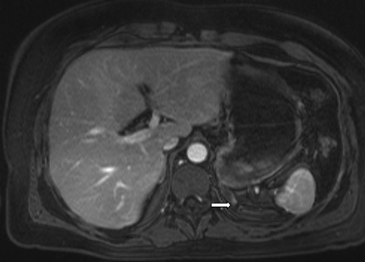

Figura 3. Glándula suprarrenal normal en resonancia magnética. (a) Cortes axial ponderado en T1 la señal de la glándula normal (flecha negra) es hipointensa respecto a la grasa retroperitoneal e isointensa respecto al parénquima hepático. (b) Cortes axial ponderado en T2 en que se muestra la glándula suprarrenal derecha (flecha blanca) y (c) corte coronal ponderado en T2 en que se muestra la glándula suprarrenal derecha (flecha blanca) y la glándula suprarrenal izquierda (flecha negra) con similares características de intendidad de señal. 3. Causas y prevalencia de las lesiones suprarrenales